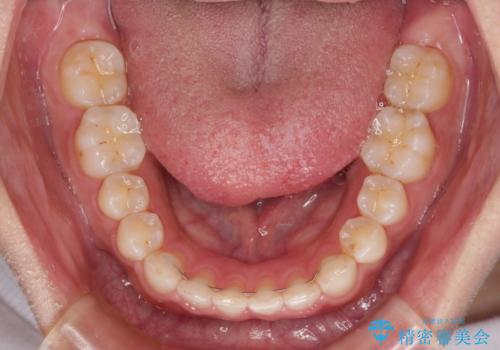

【モニター】ディープバイトを治す ワイヤー装置による矯正治療

ディープバイトが改善されたことで、食いしばりしかできなかった状態からスムーズな歯ぎしりができるようになりました。